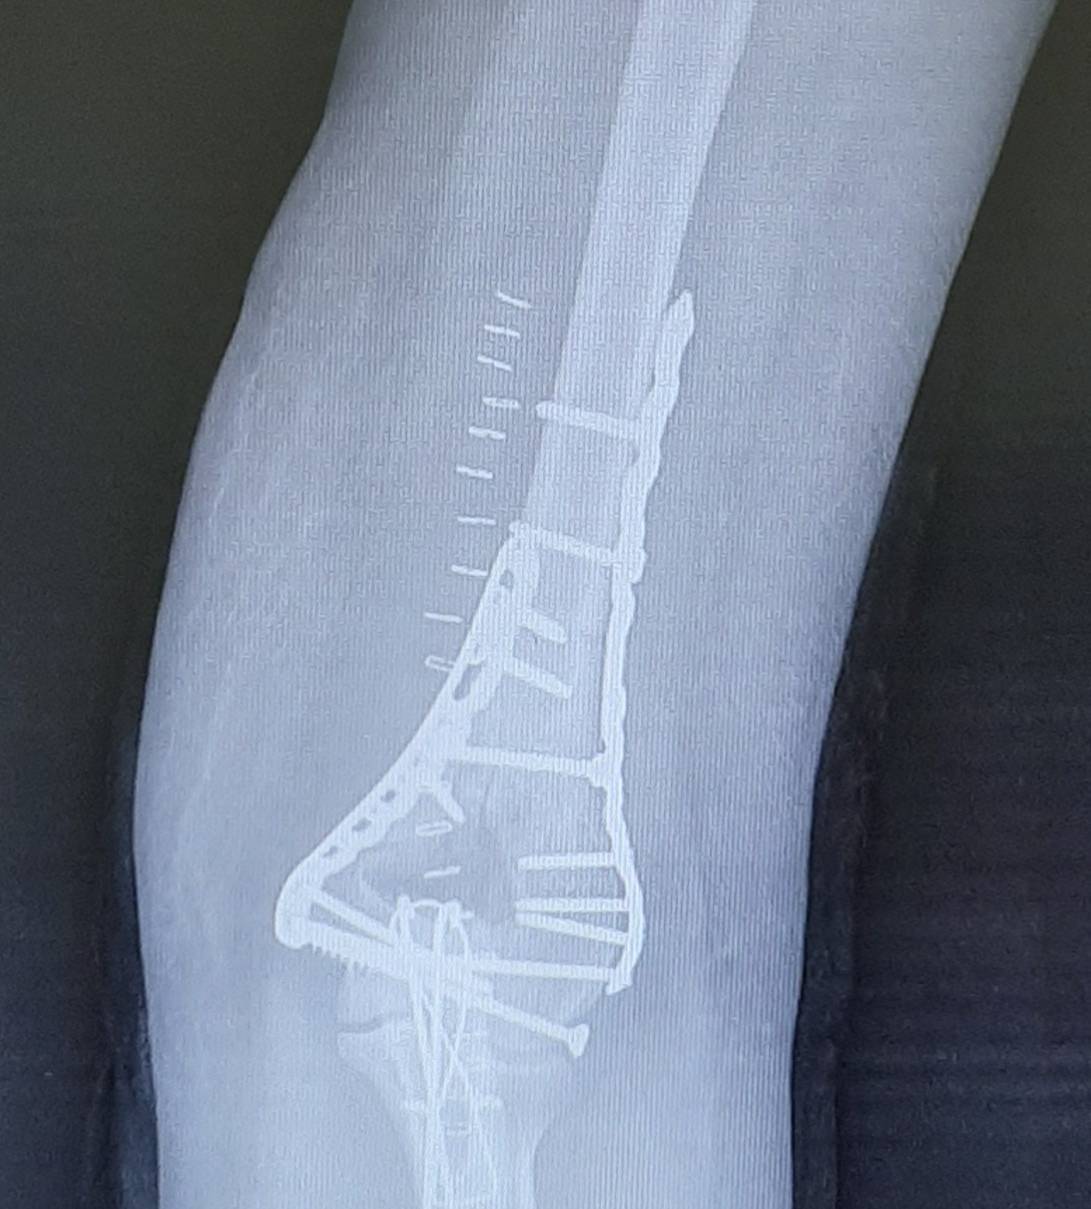

Ещё один клинический пример остеосинтеза тяжёлого перелома мыщелков плеча с использованием пластин с угловой стабильностью Synthes.

В случае настолько грубого смещения при первичном осмотре целесообразно выполнить анестезию перелома и устранить смещение с фиксацией конечности в задней гипсовой лонгтеной повязке. После обследования и предоперационной подготовки пациентка взята в операционную. Выполнен остеосинтез при помощи пластин с угловой стабильностью Synthes.

Послеоперационные рентгенограммы показывают, что смещение отломков полностью устранено, нормальные взаимоотношения костей верхней конечности восстановлены.

В ходе операции необходимо оценивать стабильность остеосинтеза к движениям в суставе, так как послеоперационный протокол предполагает раннюю нагрузку уже через 1-2 дня после операции. Ранние движения в суставе препятствуют образованию грубых рубцов и спаек, которые в противном случае могут вызвать стойкое ограничение движений в суставе.